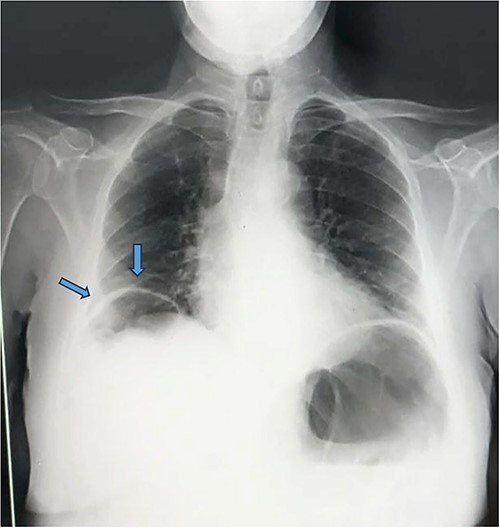

We then proceeded by performing a blood work, which revealed an elevated white blood cell count of 15.40 × 1,000/𝜇l (4.8–10.8), with a C-Reactive Protein level at 80. Simultaneously, a chest X-ray revealed air beneath the right diaphragmatic dome, suggestive of pneumoperitoneum (Fig. 1).

Appearance of pneumoperitoneum beneath the right diaphragmatic dome.